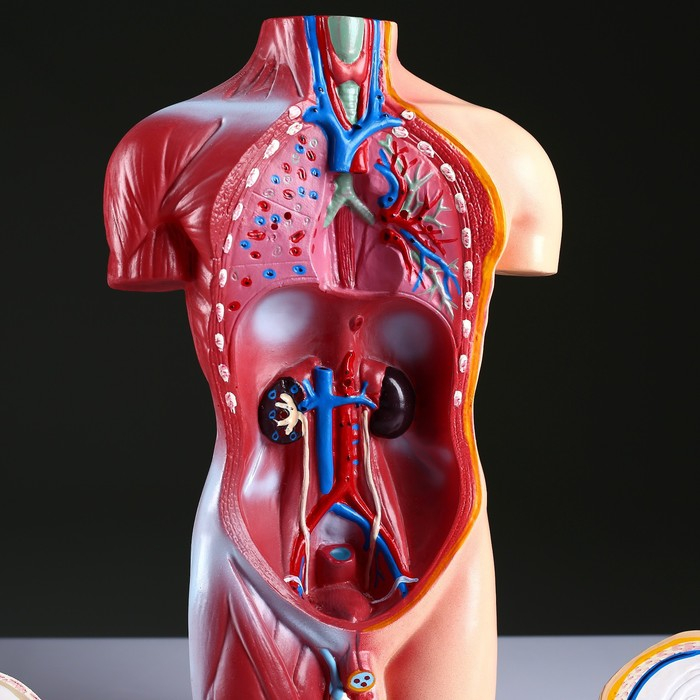

ЕКБ 93

No Brand, артикул: 7072363